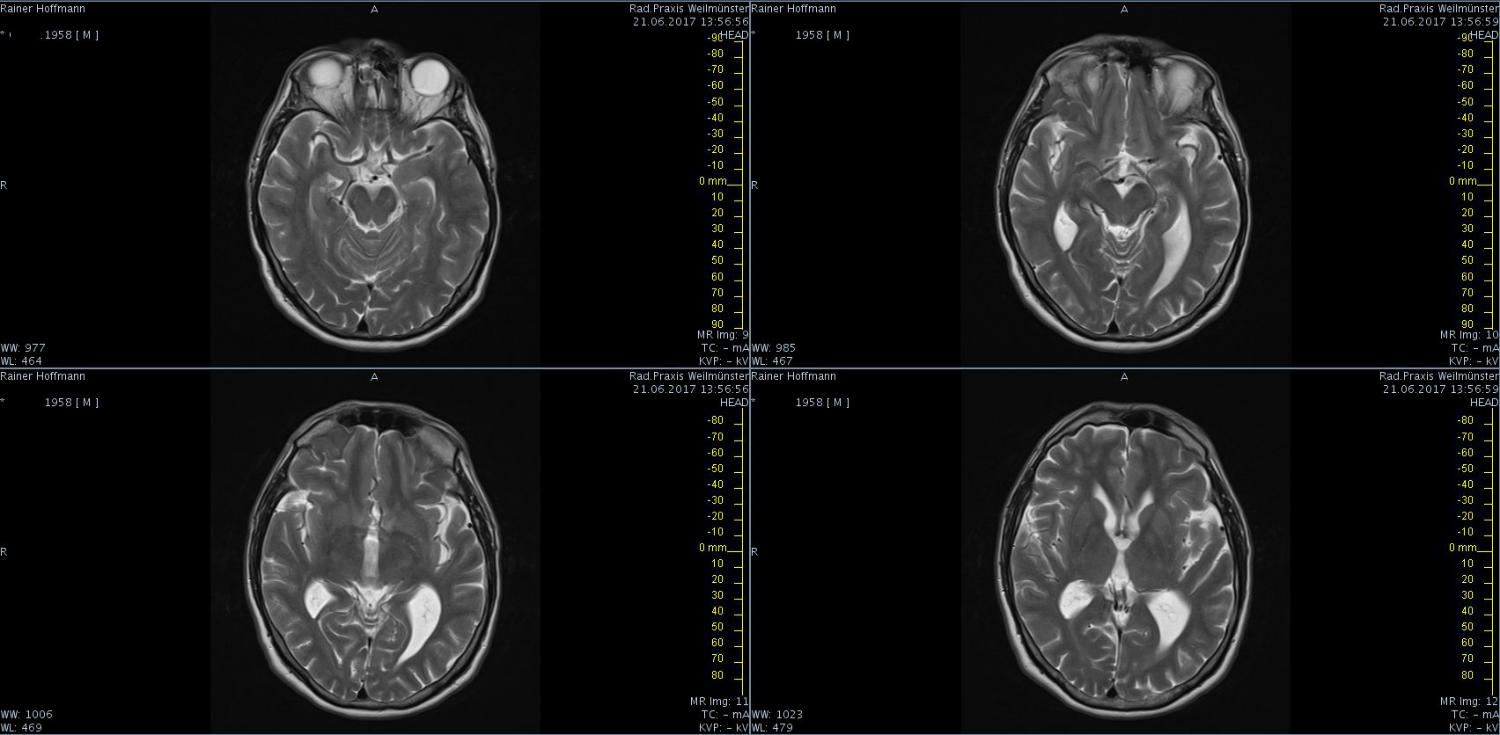

Das ist ja ganz toll, dass Ihr die Seite so schnell gefunden habt. Ich zeige euch jetzt ein ganz, ganz anderes Paßfoto von mir. Es könnte Ähnlichkeiten zu anderen lebenden oder bereits verstorbenen Personen geben. Wenn Ihr das erste Bild oben links anklickt wird es ver- größert dargestellt. Dann kann man mit den Pfeiltasten am unteren Bild- rand durch meinen Kopf blättern. Es gibt nicht viel zu sehen. Vielen Dank an Martina für Ihre Hilfe.

MRT